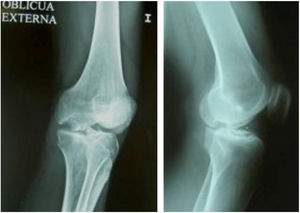

The surgical technique used comprised an internal or external knee arthrotomy, followed by preparation of the damaged area using the Maxioats® (Artrhex®) technique23 (Figs. 1 and 2).

Two patients required special milling of the graft, as the Maxioats® technique did not cover the defect; one received a double graft and, at one year, arthroscopic control of the graft (Figs. 3 and 4); in the other case, the graft was milled by hand, given the defect, and fixed with 2 Herbert screws (Figs. 5 and 6).

Plain anteroposterior and lateral studies of the joint were used for postoperative radiographic measurement, to check the correct implantation of the graft in all cases, with no loosening or subsequent mobilisation observed, except in one case where the graft had collapsed slightly due to partial integration.